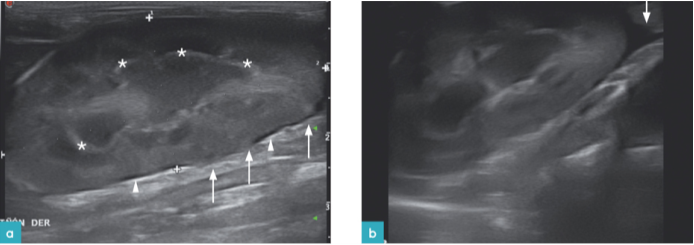

高回声的三角形截面显现存在肾皮质的慢性肾梗塞,其中肾梗塞是由于弓形动脉阻塞而导致的肾锥体血流量不足引发(图16和17.视频7和8)。一些作者将肾梗塞描述为节段性或三角形的皮层病变,该病变主要会引起肾囊强回声。急性肾梗塞会表现出低回声或混合回声。随着急性肾梗塞发展成慢性长期性梗塞,会出现回声增强,外周萎缩从而导致肾囊凹陷。梗塞可能继发于血栓发生增加的过程中,如甲状腺机能亢进,肿瘤或心肌病。

在一项针对600只猫的研究(其中的309例被诊断患有肾梗塞)报告中发现,患有肥厚性心肌病的成年猫和老年猫(7到14岁)相较于其他猫来说,更有可能患有肾梗塞。此外,患有肾梗塞的猫可能同时患有主动脉血栓栓塞,但没有证据表明这与甲状腺功能亢进或肿瘤的发生有关。一项对布偶猫的研究显示,由于布偶猫对皮层病变的易感性较高,所以肾囊不规则或呈波浪状的发生率较高。